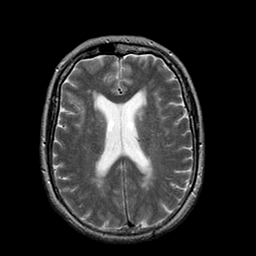

Stroke:T2-weighted MR #1 -- Slice #15

[Home][Help][Clinical] Slice 15